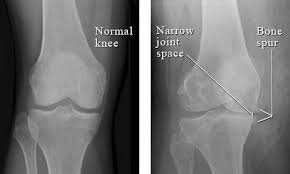

The patella or kneecap is seen sitting in front and to the left of the femur. A lateral view x ray shows the knee from the side. The image here is a front to back view of the knee joint also called the ap view.

Find x ray of knee stock images in hd and millions of other royalty free stock photos illustrations and vectors in the shutterstock collection. Add to likebox 127713977 wheelchair icon simple style. X ray image of right knee ap and lateral view showing total knee arthroplasty and fractures of the tibial plateau with. This x ray shows a healthy joint with nice sharp well defined edges at the joint margins.